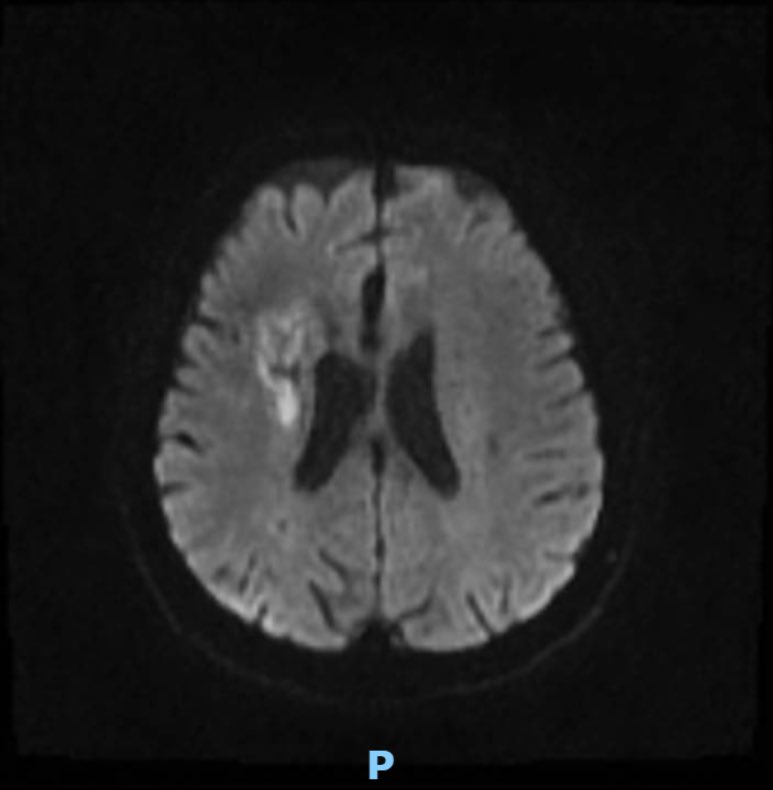

This 🧔♂️ presents with a subarachnoid haemorrhage in the left suprasellar cistern

DSA shows an infundibulum/ aneurysm of the left PCom. To coil or not was a conundrum. Every expert has a different take

The literature says anything over 3 mm is an aneurysm…

The size is 3.4 mm x 2.6 and it is located in the region of the bleed.